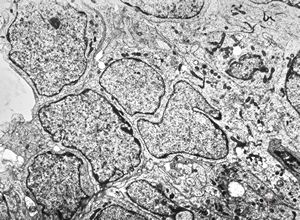

M,55y. | meningotheliomatous meningeoma

F,75y. | meningotheliomatous meningeoma